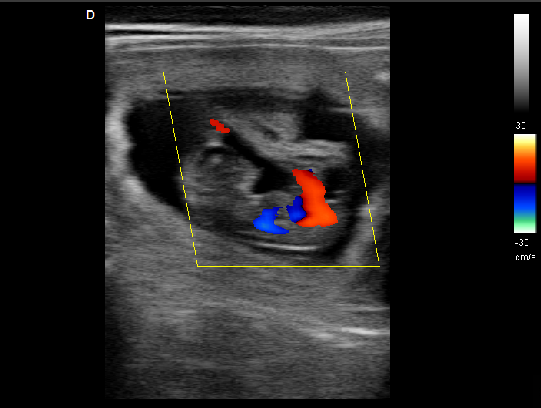

P5-VET便攜獸用彩超機適用對象:

牛羊馬豬犬貓及多種家禽、實驗動物、野生動物、及部分水生動物。

P5-VET獸用彩超機應用范圍:

適用于各種動物的臨床腹部、胸腔,心臟、肌腱、小器官、眼球、生殖系統等的檢查